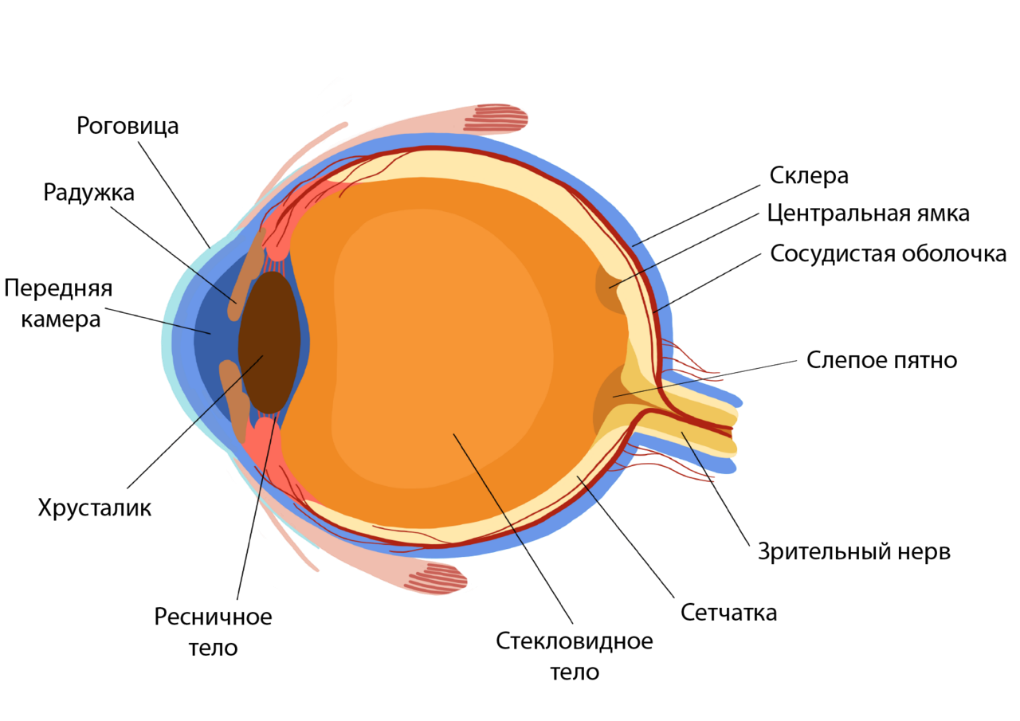

КТ-графики и изображение строения глаза